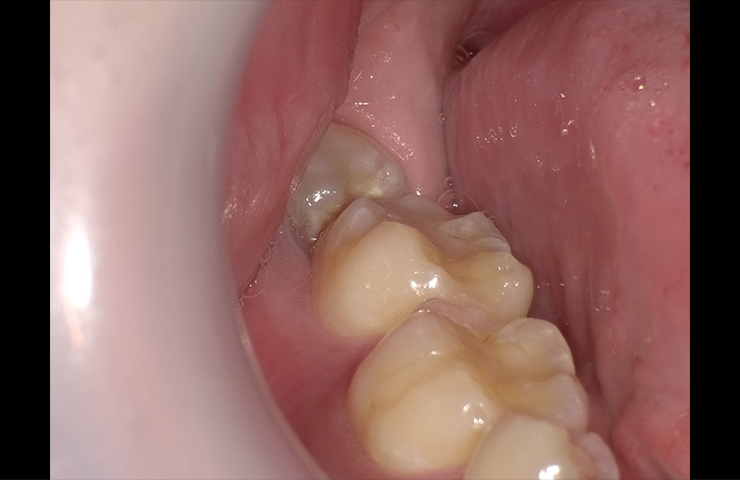

親知らずの生え方 まっすぐタイプ 上記症例写真は、親知らずがまっすぐ生えていて、上の歯と噛み合っているのでちゃんと磨ければ残せるケースです。 黄色い線は神経の通っている管を示します。 親知らずは抜かなくてもいい場合があります 11親知らずには大きく分けて3種類の生え方がある 12親知らずは抜かなければいけないものではない 13真横に生えてきている場合のデメリット 2真横に生えた親知らずを抜く場合の方法や痛み 21歯茎を少し切ってから抜歯をする 22抜歯後は腫れや痛み のまとめ 親知らずは何歳から生える? 通常の永久歯との違い 親知らずが生えるのは、 大体10代後半~代前半の時期 です。 少数ではありますが、30代に入ってから親知らずが生えてくる方もいます。 また、親知らずが生えていないように見えても